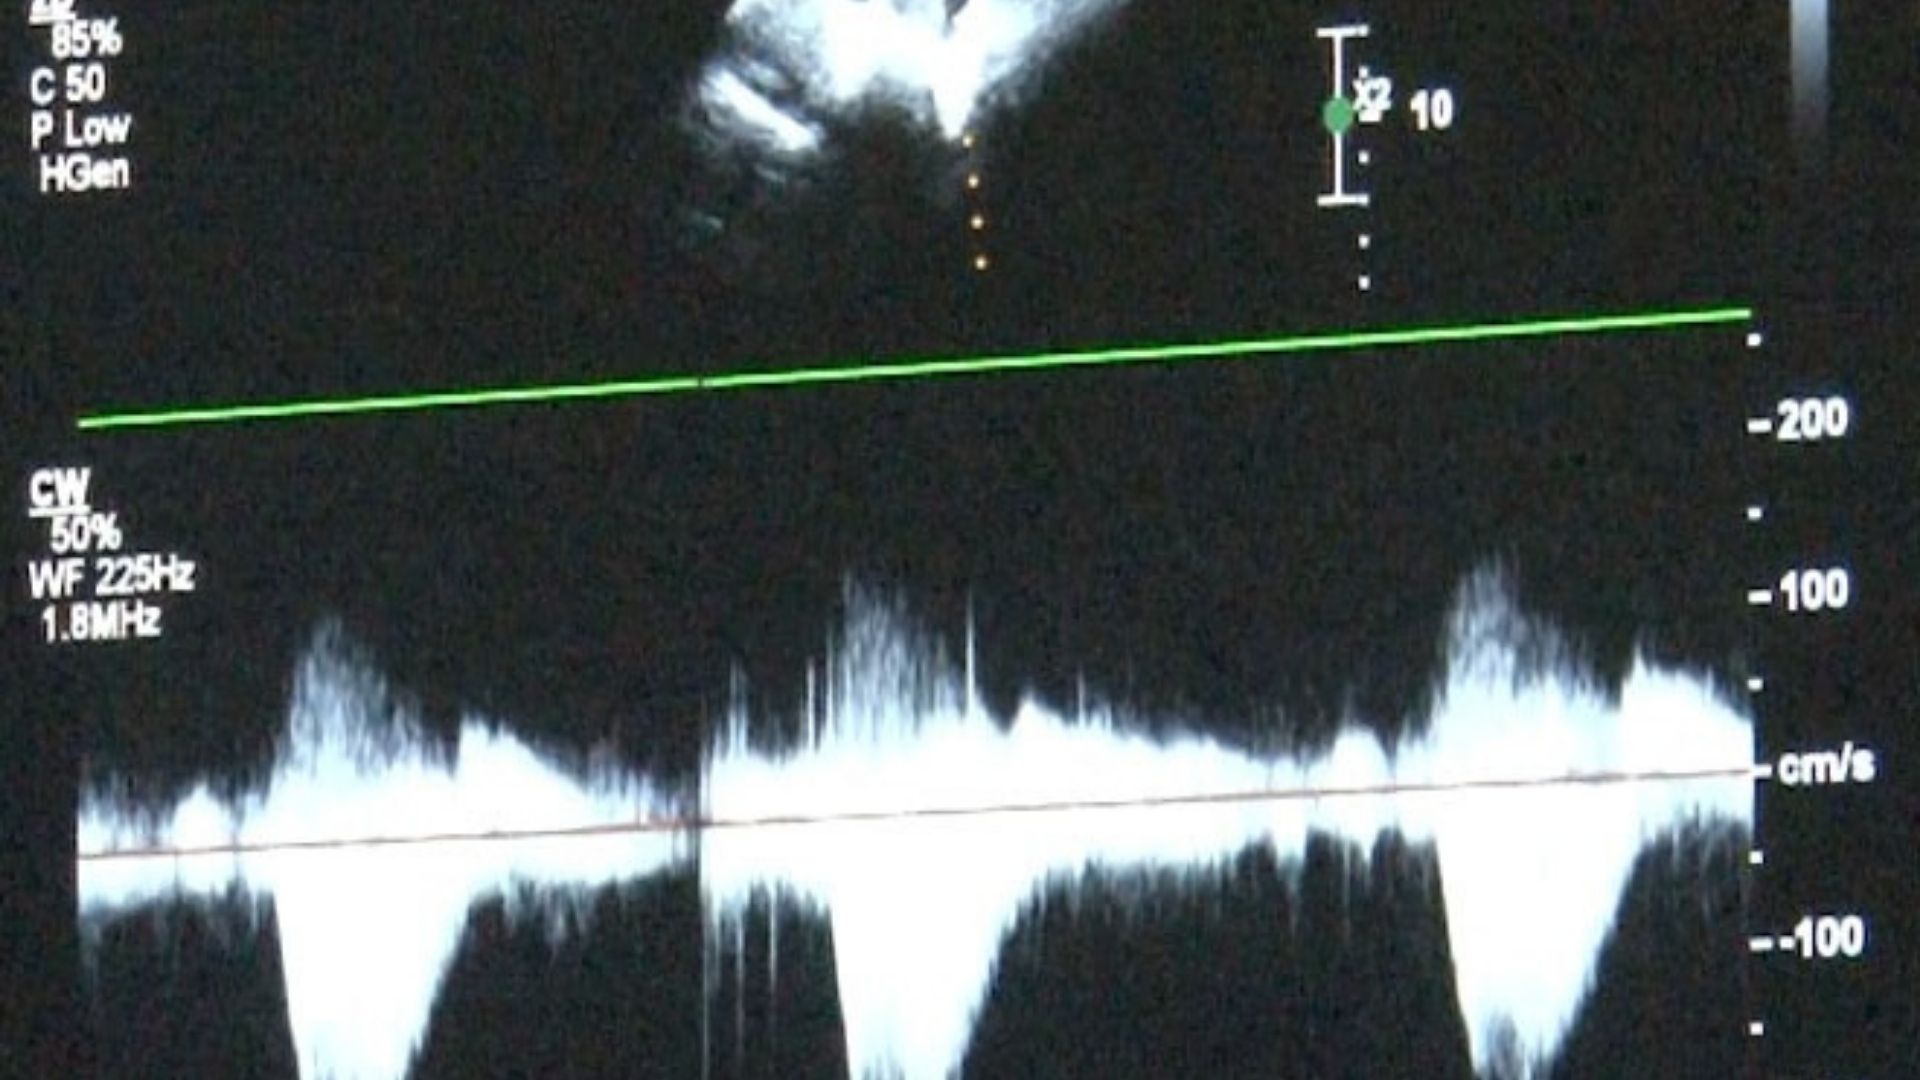

Kanuni Sultan Süleyman Eğitim ve Araştırma Hastanesi’nden Uzm. Dr. Damla Gökçeer Akbulut, doğumsal kalp hastalıklarının çeşitli nedenlerle ortaya çıkabileceğini belirterek, fetal ekokardiyografi sayesinde bebeklerin anne karnındayken teşhis edilebildiğini söyledi. Akbulut, “Bazı bebeklerde morarma gibi bulgular doğumda görülürken bazıları ilk ay içinde belirginleşiyor” dedi.

Uzm. Dr. Akbulut, hızlı nefes alıp verme, morarma veya emerken terleme gibi belirtilerin acilen çocuk kardiyolojisine yönlendirilmesi gerektiğini vurguladı. Anne karnında tanı konulamayan durumlarda doğar doğmaz ekokardiyografiyle hastalığın tespit edilebildiğini söyleyen Akbulut, özellikle RSV ve influenza dönemlerinde kalp hastası çocukların risk altında olduğunu belirtti.